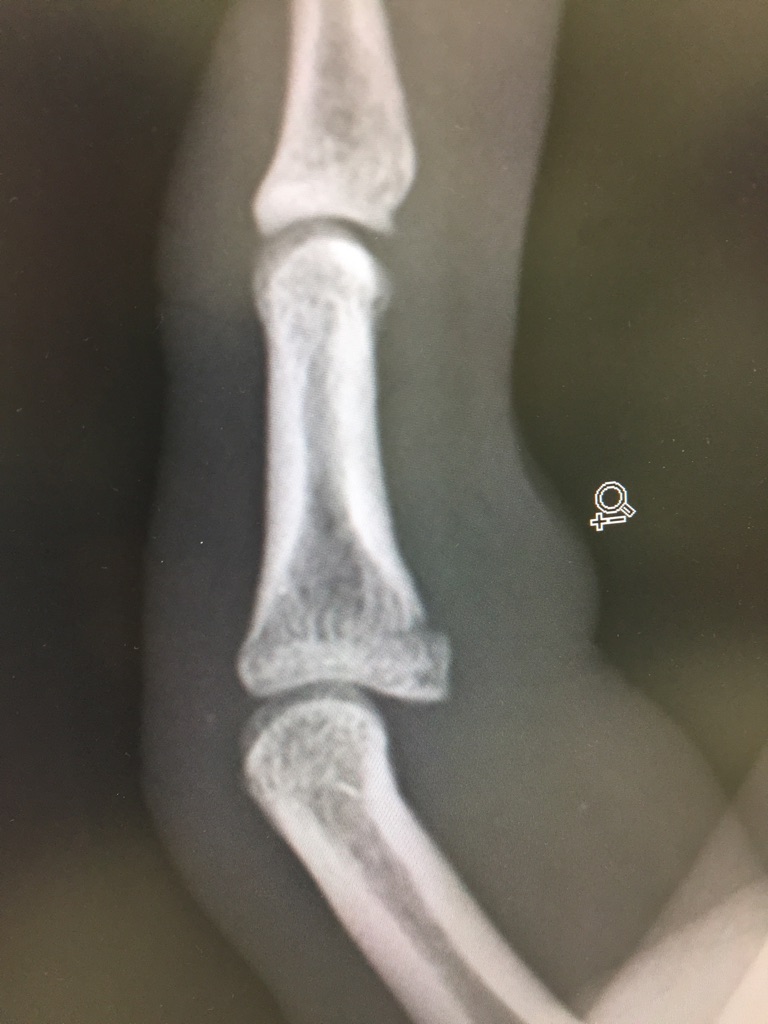

所見:左第5中節骨基部(+)基節骨(+)中手骨頸部(±)

腫脹(+)皮下出血斑(±)MP及びPIP ROM制限(+)

診断名:左第5指中節骨基部骨折(掌側裂離)